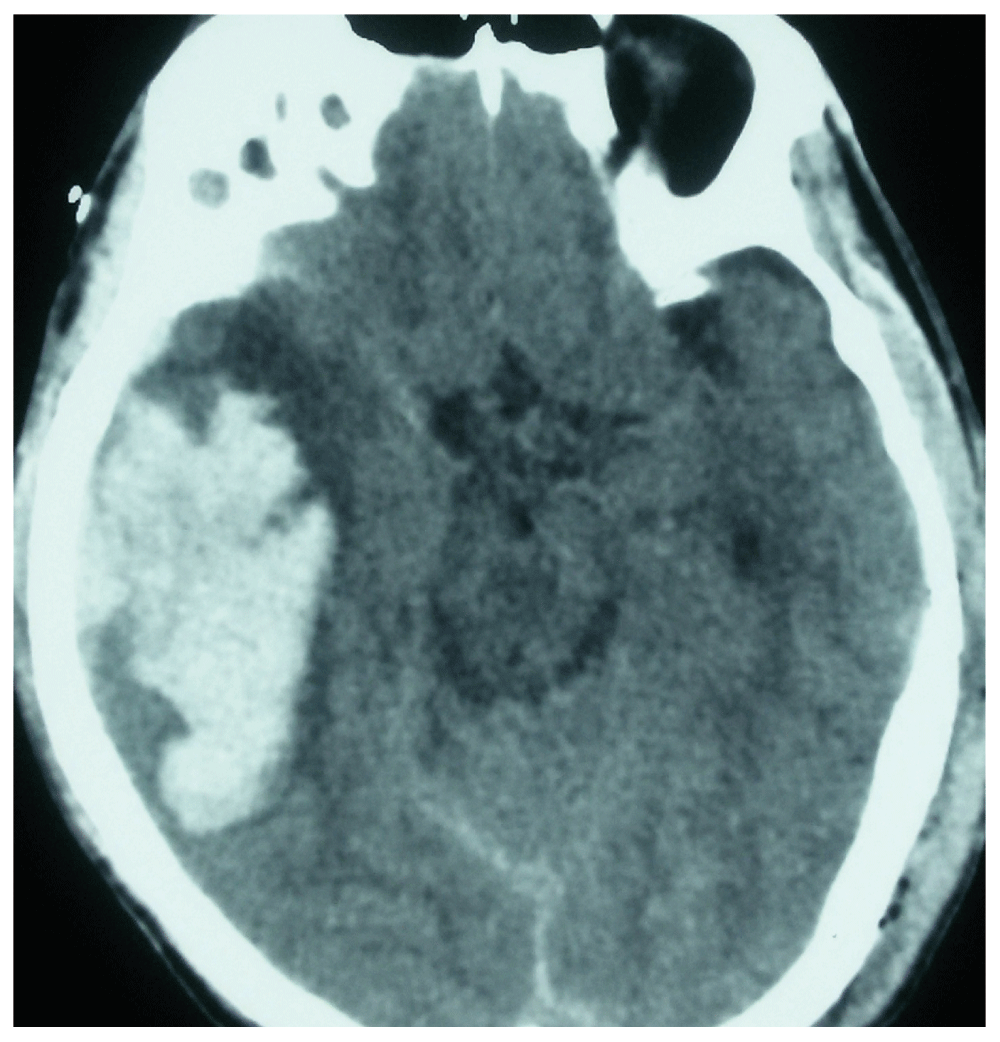

A 50-year-old male from Siraha, a distant village in Nepal, was referred to our neurosurgical centre following a road traffic accident after being hit by a speeding car. The patient had a brief loss of consciousness and a single episode of vomiting following the incident. There was no history of seizurogenic activity observed during the transfer. On arrival to the emergency department, his Glasgow coma scale (GCS) was E3M6V5 with no paucity in movement of any limbs. His vital parameters were within normal range with blood pressure of 130/90, pulse rate of 86/min and oxygen saturation of 99% in room air. It was difficult to assess differences in pupillary size as he had corneal opacity on the left eye, resulting from an injury sustained during his childhood. However, on close examination, we observed that there was prominence of the forehead wrinkles on the right half of his face especially when the patient was trying to open his eyes during conversation, which we termed as frontalis sign (Figure 1). The wrinkles on the contra lateral half were normal with no abnormal deviation of angle of the mouth dismissing the differential diagnosis of upper facial nerve palsy. Because of the finding, we suspected impending uncal herniation in the patient and thereby advised for an emergency computed tomography (CT) scan of the head. It revealed right sided huge temporo-parietal contusion with thin fronto-temporo-parietal subdural hematoma with features of uncal herniation (Figure 2). The condition was explained to his relatives and they were counseled for emergency evacuation of the hematoma. On their consent, we performed a craniotomy, evacuation of the subdural hematoma and removal of the contusion. Following the procedure, the brain was lax and pulsatile. The patient was extubated without any untoward events in the postoperative period. The frontalis sign diminished following the surgery (Figure 3). The post operative scan confirmed resolution of the mass effect and normalization of the cisternal anatomy (Figure 4). The patient was started on Levtiracetam 500 mg intravenously every 12 hours which was changed to oral medication after three days as seizure prophylaxis. The patient was discharged after suture removal on the 8th postoperative day. The patient followed up in the outpatient clinic 2 weeks later in sound health. Eye opening was near normal. The patient was advised for monthly follow up.